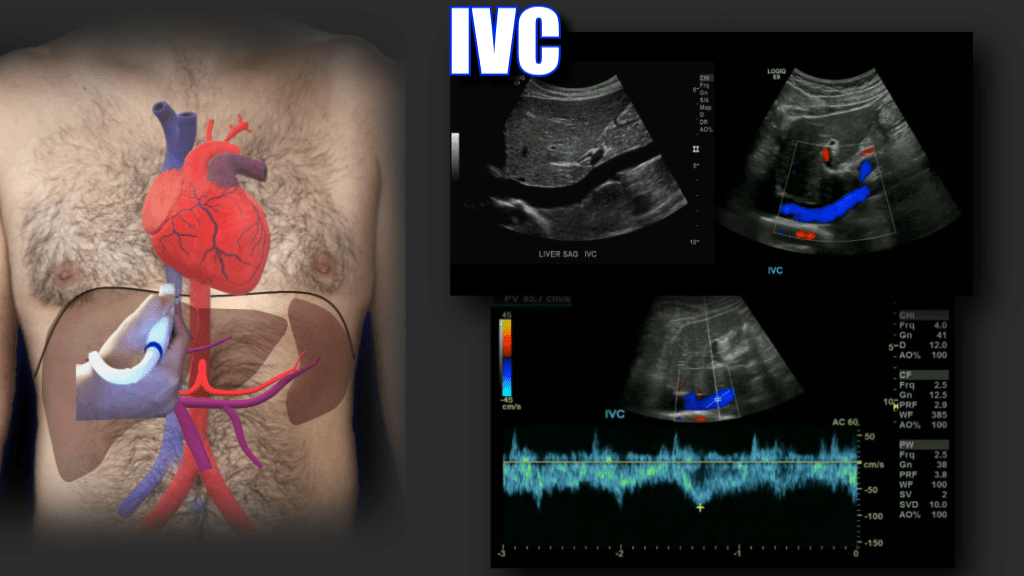

When the portal vein enters the liver it bifurcates into right and left main branches. The right portal vein bifurcates into an anterior and posterior branch which feed segments 5, 6, 7 and 8 respectively, whereas the left branch feeds segments 2, 3 and 4. The normal diameter of the main portal vein is 1.3 cm (some institutions use 15. as the upper limit) Normal flow is hepatopetal (towards the liver), with a flow velocity between 15-40 cm/s. Be sure to make sure you color is inverted and your approach is optimized. In the main portal vein below flow is hepatopetal in both images, the only difference is transducer angle, tilt and approach.